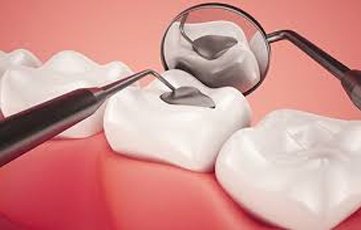

By closing off spaces where bacteria can enter, a filling also helps prevent further decay. Materials used for fillings